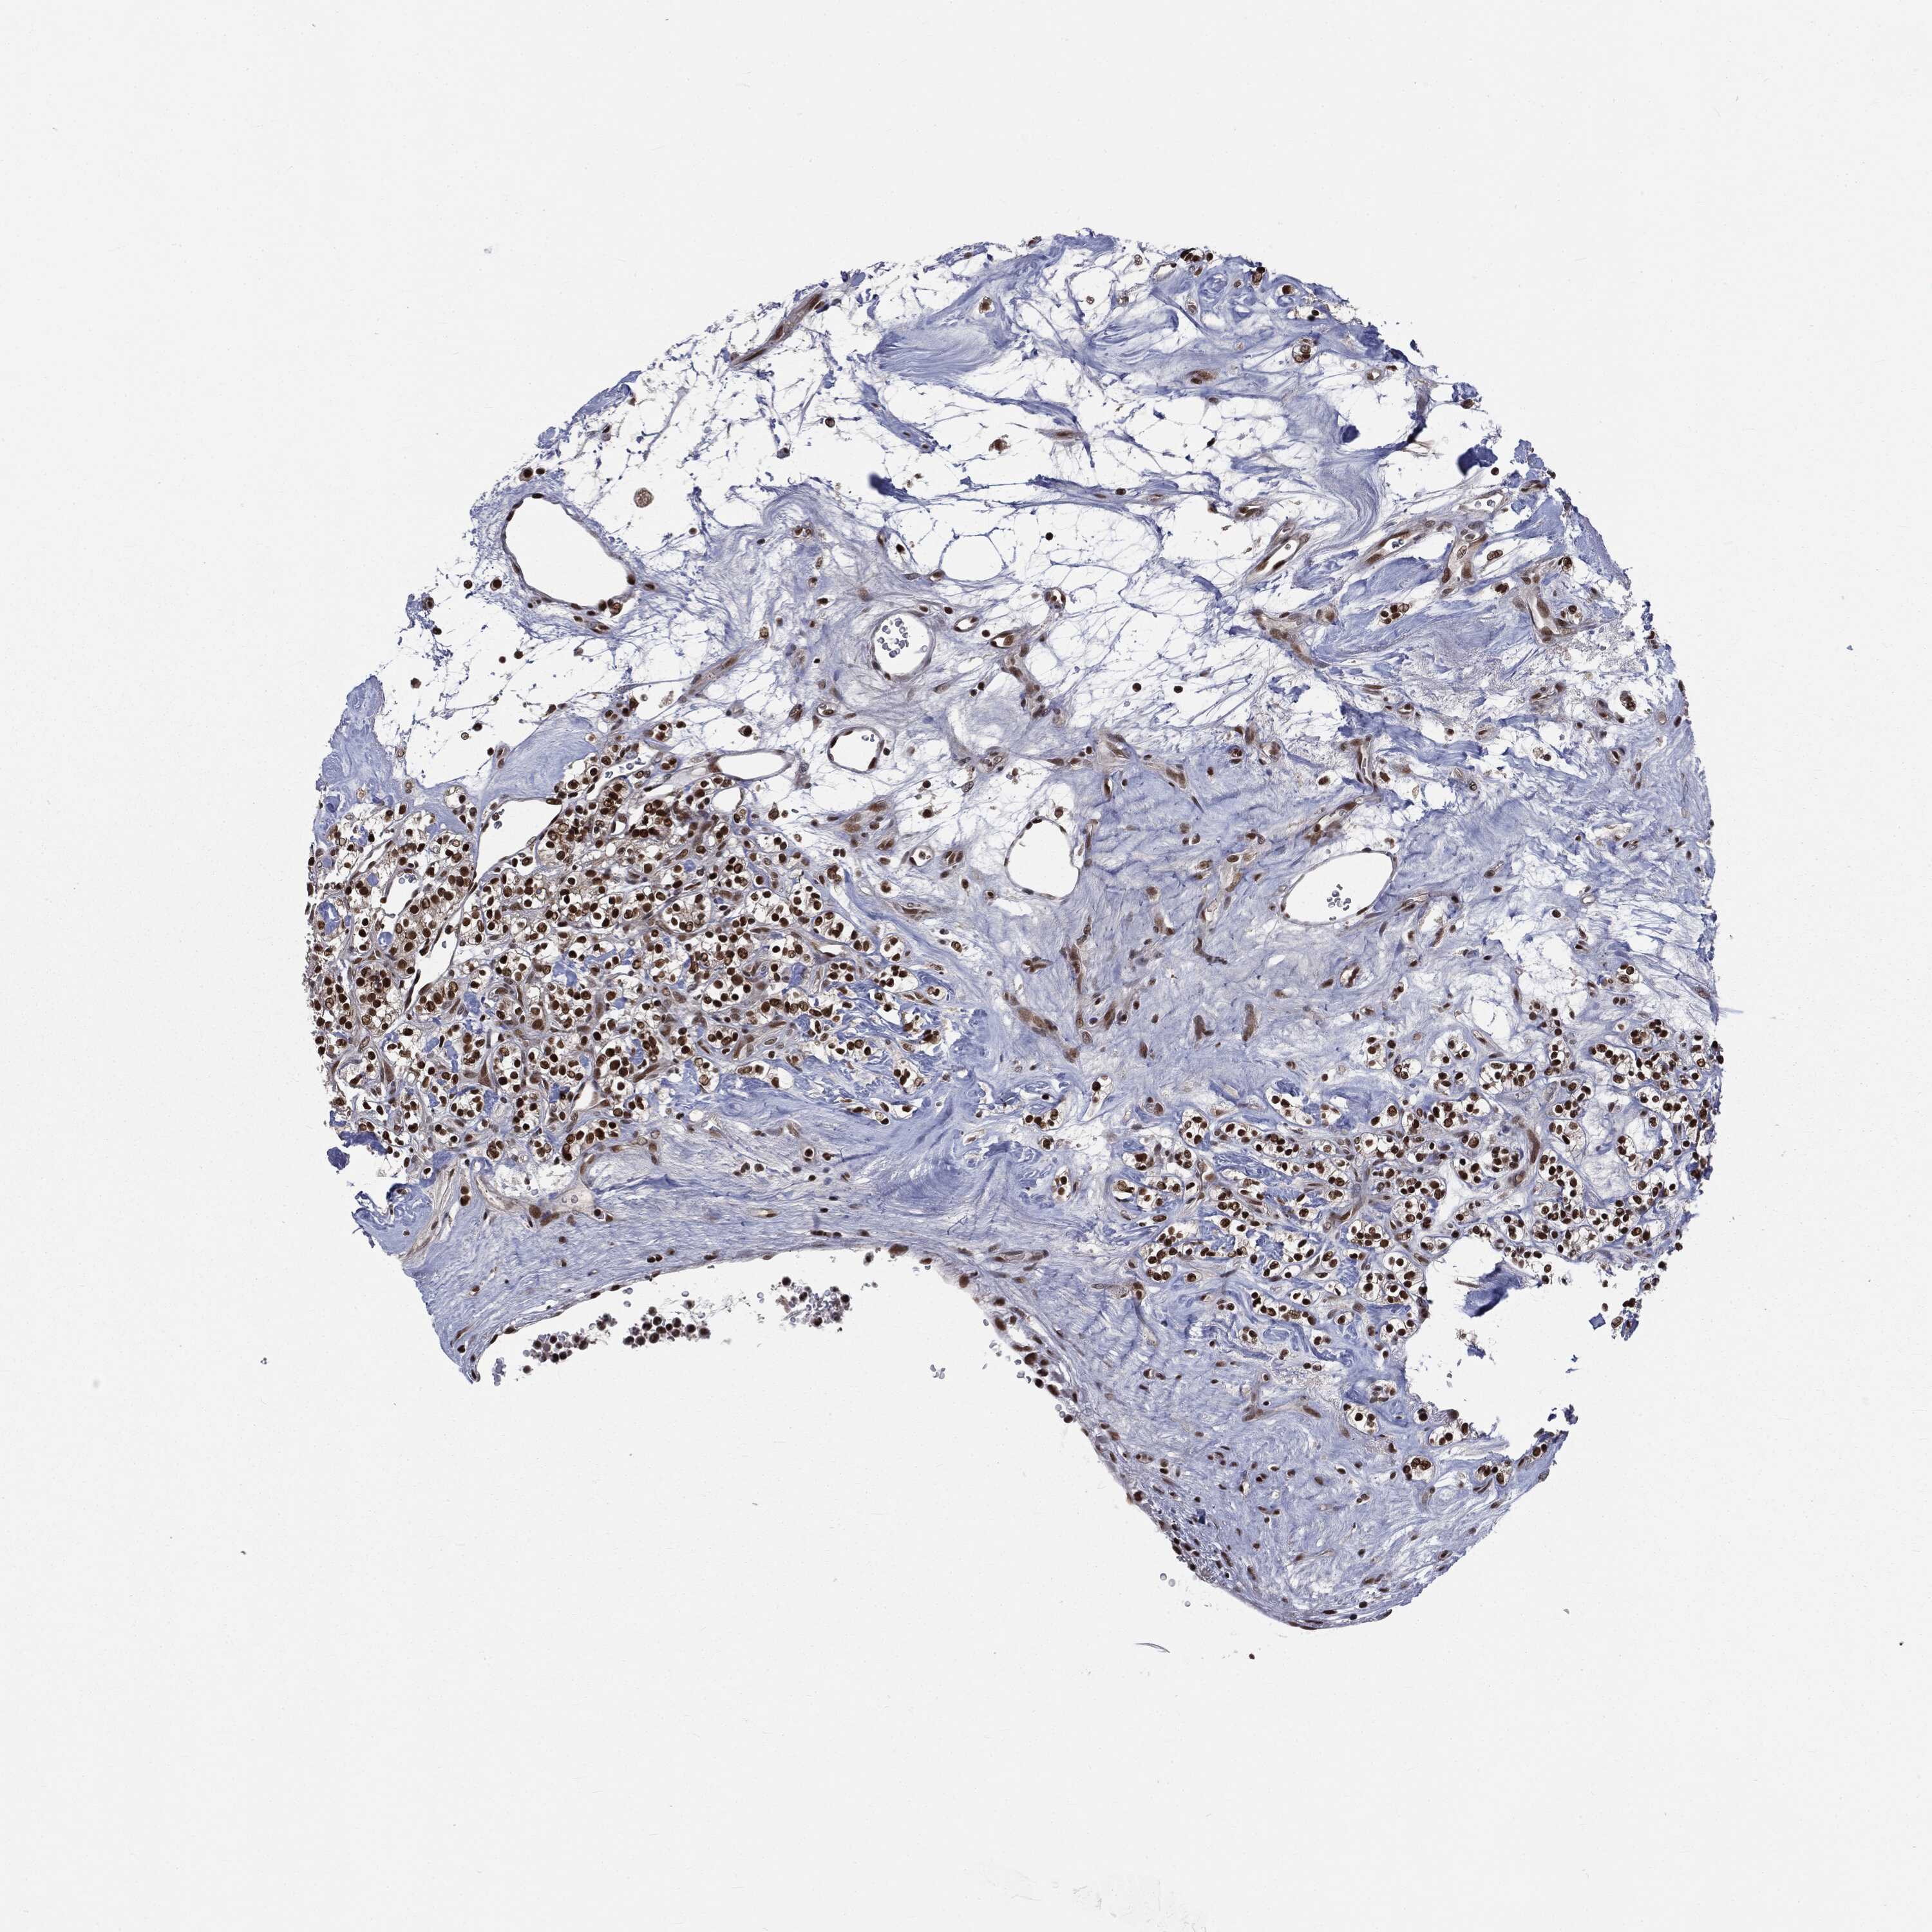

KIDNEY RENAL CLEAR CELL CARCINOMA (VALIDATION) - Interactive survival scatter ploti

The Survival Scatter plot shows the clinical status (i.e. dead or alive) for all individuals in the patient cohort, based on the same data that underlies the corresponding Kaplan-Meier plots. Patients that are alive at last time for follow-up are shown in blue and patients who have died during the study are shown in red.

The x-axis shows the expression levels (FPKM) of the investigated gene in the tumor tissue at the time of diagnosis. The y-axis shows the follow-up time after diagnosis (years). Both axes are complimented with kernel density curves demonstrating the data density over the axes. The top density plot shows the expression levels (FPKM) distribution among dead (red) and alive patients (blue). The right density plot shows the data density of the survived years of dead patients with high and low expression levels respectively, stratified using the cutoff indicated by the vertical dashed line through the Survival Scatter plot. This cutoff is automatically defined based on the FPKM cutoff that minimizes the p-score. The cutoff can be changed by dragging the vertical line or by entering a cutoff value in the square labeled "Current cut-off".

Under the Survival Scatter plot the p-score landscape (black curve; left axis) is shown together with dead median separation (red curve; right axis). Dead median separation is the difference in median mRNA expression between patients who have died with high and low expression, respectively. It is calculated as follows: median FPKM expression of dead patients with high expression - median FPKM expression of dead patients with low expression. This is intended to aid the user in visually exploring custom cutoffs and the associated p-scores and dead median separation.

Individual patient data is displayed and can be filtered by clicking on one or more of the category buttons on the top of the page. Categories describing expression level and patient information include: high, low, alive, dead, female, male and tumor stages. The scale of the x-axis can be toggled between linear and log-scale by clicking on the "x log" button. Mouse-over function shows TCGA ID, patient information and mRNA expression (FPKM) for each patient.

& Survival analysisi

Kaplan-Meier plots summarize results from analysis of correlation between mRNA expression level and patient survival. Patients were divided based on level of expression into one of the two groups "low" (under cut off) or "high" (over cut off). X-axis shows time for survival (years) and y-axis shows the probability of survival, where 1.0 corresponds to 100 percent.

DPH2 is not prognostic in Kidney Renal Clear Cell Carcinoma (validation)

Best expression cut offi

Based on the FPKM value of each gene, patients were classified into two groups and association between prognosis (survival) and gene expression (FPKM) was examined. The best expression cut-off refers the FPKM value that yields maximal difference with regard to survival between the two groups at the lowest log-rank P-value. Best expression cut-off was selected based on survival analysis .

When clicking on this number, the vertical dashed line indicating cut-off, the interactive survival plot, and the Kaplan-Meier curve will be adjusted to show results based on the best expression cut-off.

: 10.68

TCGA RNA samplesi

RNA-seq data is reported as average FPKM (number Fragments Per Kilobase of exon per Million reads), generated by the The Cancer Genome Atlas (TCGA) .

Normal distribution across the dataset is visualized with box plots, shown as median and 25th and 75th percentiles. Points are displayed as outliers if they are above or below 1.5 times the interquartile range. FPKM values of the individual samples are presented next to the box plot.

Average pTPM 10.1

Number of samples 100